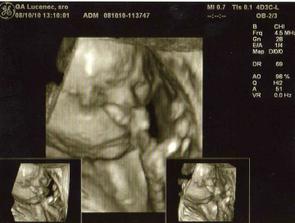

Nase 3D sono